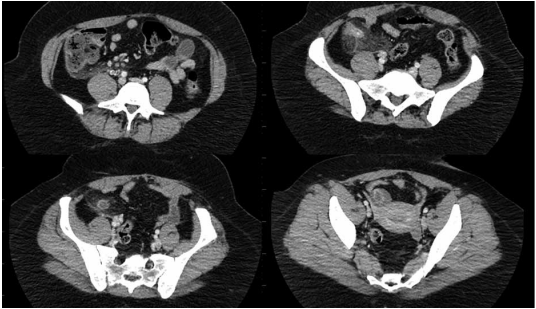

Paciente de 26 anos, sexo feminino, vem com queixa de mal-estar há dois dias, com piora progressiva e, há um dia,

com dor abdominal em hipogastro associada a disúria e polaciúria. Nega febre, nega alterações de hábito intestinal,

refere inapetência, mas nega vômitos. Sexualmente ativa, refere corrimento amarelo claro no período, faz uso de contraceptivo oral; data da última menstruação há 3 semanas. Ao exame físico, está em bom estado geral, FC 89 bpm,

PAM 120 x 87 mmHg, dor à palpação de hipogastro, sem massas palpáveis ou sinal de irritação peritoneal. Urina I com

20000 leucócitos/mL (VR 0 – 10000). Realizou o exame a seguir.

(Arquivo pessoal; imagem usada com autorização)

Assinale a alternativa que contém o diagnóstico correto para esse caso.